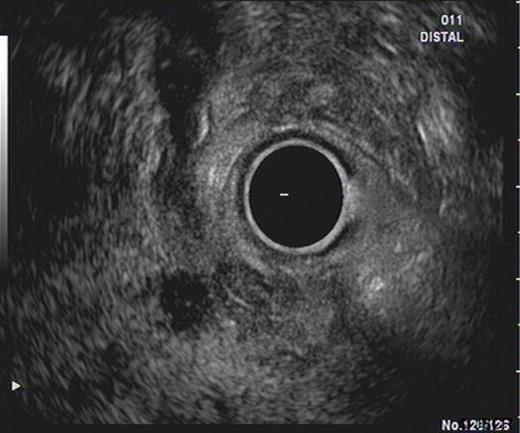

An ultrasound prior to this clinic appointment revealed a dilated Common Bile Duct (CBD) of up to 10mm, a distended thin walled gallbladder, no calculi and a normal pancreatic body. The head of the pancreas was not visualised. Laboratory tests from the GP revealed an elevated bilirubin of 150 umol/L. The CT of his abdomen and pelvis confirmed a dilated CBD and some areas of focal calcification on the head of the pancreas (Figure 3). The EUS demonstrated a thickened distal CBD with a 1.5cm hypoechoic lesion in the pancreatic head (Figure 4). The HPB MDT meeting suspected a malignant lesion and felt that a Whipple’s procedure would offer the best chance of cure.

EUS demonstrating lesion at the pancreatic head with thickening of distal CBD